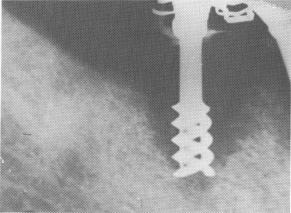

When too little alveolar bone height remains and if post type implants are used, the implants may

Fig. 14-1. Bone resorption rapidly occurs where the open spirals are not deeply buried in the bone. In this case, a rapid invagination of the epithelium through the spirals that were near the alveolar crest took place, preventing the bone regeneration from growing closer to the implants. (From Linkow, L. I.: Clinical evaluation of the various designed endosseous implants, J. Oral Implant Transplant Surg. 12:35-46, 1966.)

eventually fail because of soft tissue invagination. A 2- or 3-mm. invagination is harmless, providing that the narrow abutment post, not the open spirals, is embedded in the area. Otherwise a rapid invagination of the epithelial tissue occurs in and between the spirals, preventing the regeneration of bone or